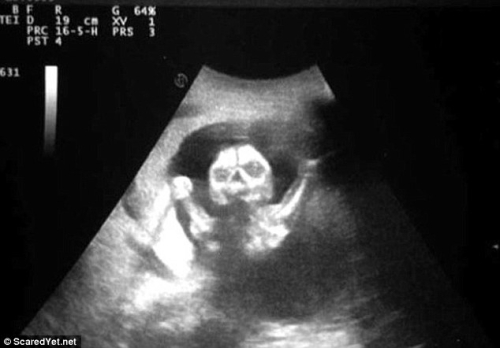

영국 데일리메일은 각각 다른 발달 단계에서 무시무시한 모습을 하고 있는 태아의 사진들을 소개했다. 어떤 사진은 공포 영화의 한 장면과 같은 모습을 보여준다.